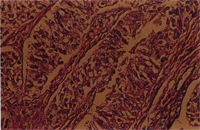

組織病變 : 可見豐富結締組織(以成熟纖維為主)形成支架,分隔著生精小管。而生精小管之管腔中幾乎為質淡染、具有細小空泡、且核呈卵圓至橢圓、淡染核仁明顯之腫瘤細胞所填滿。腫瘤細胞大小一致,呈長多邊形到長三角形(圖3, 4)。